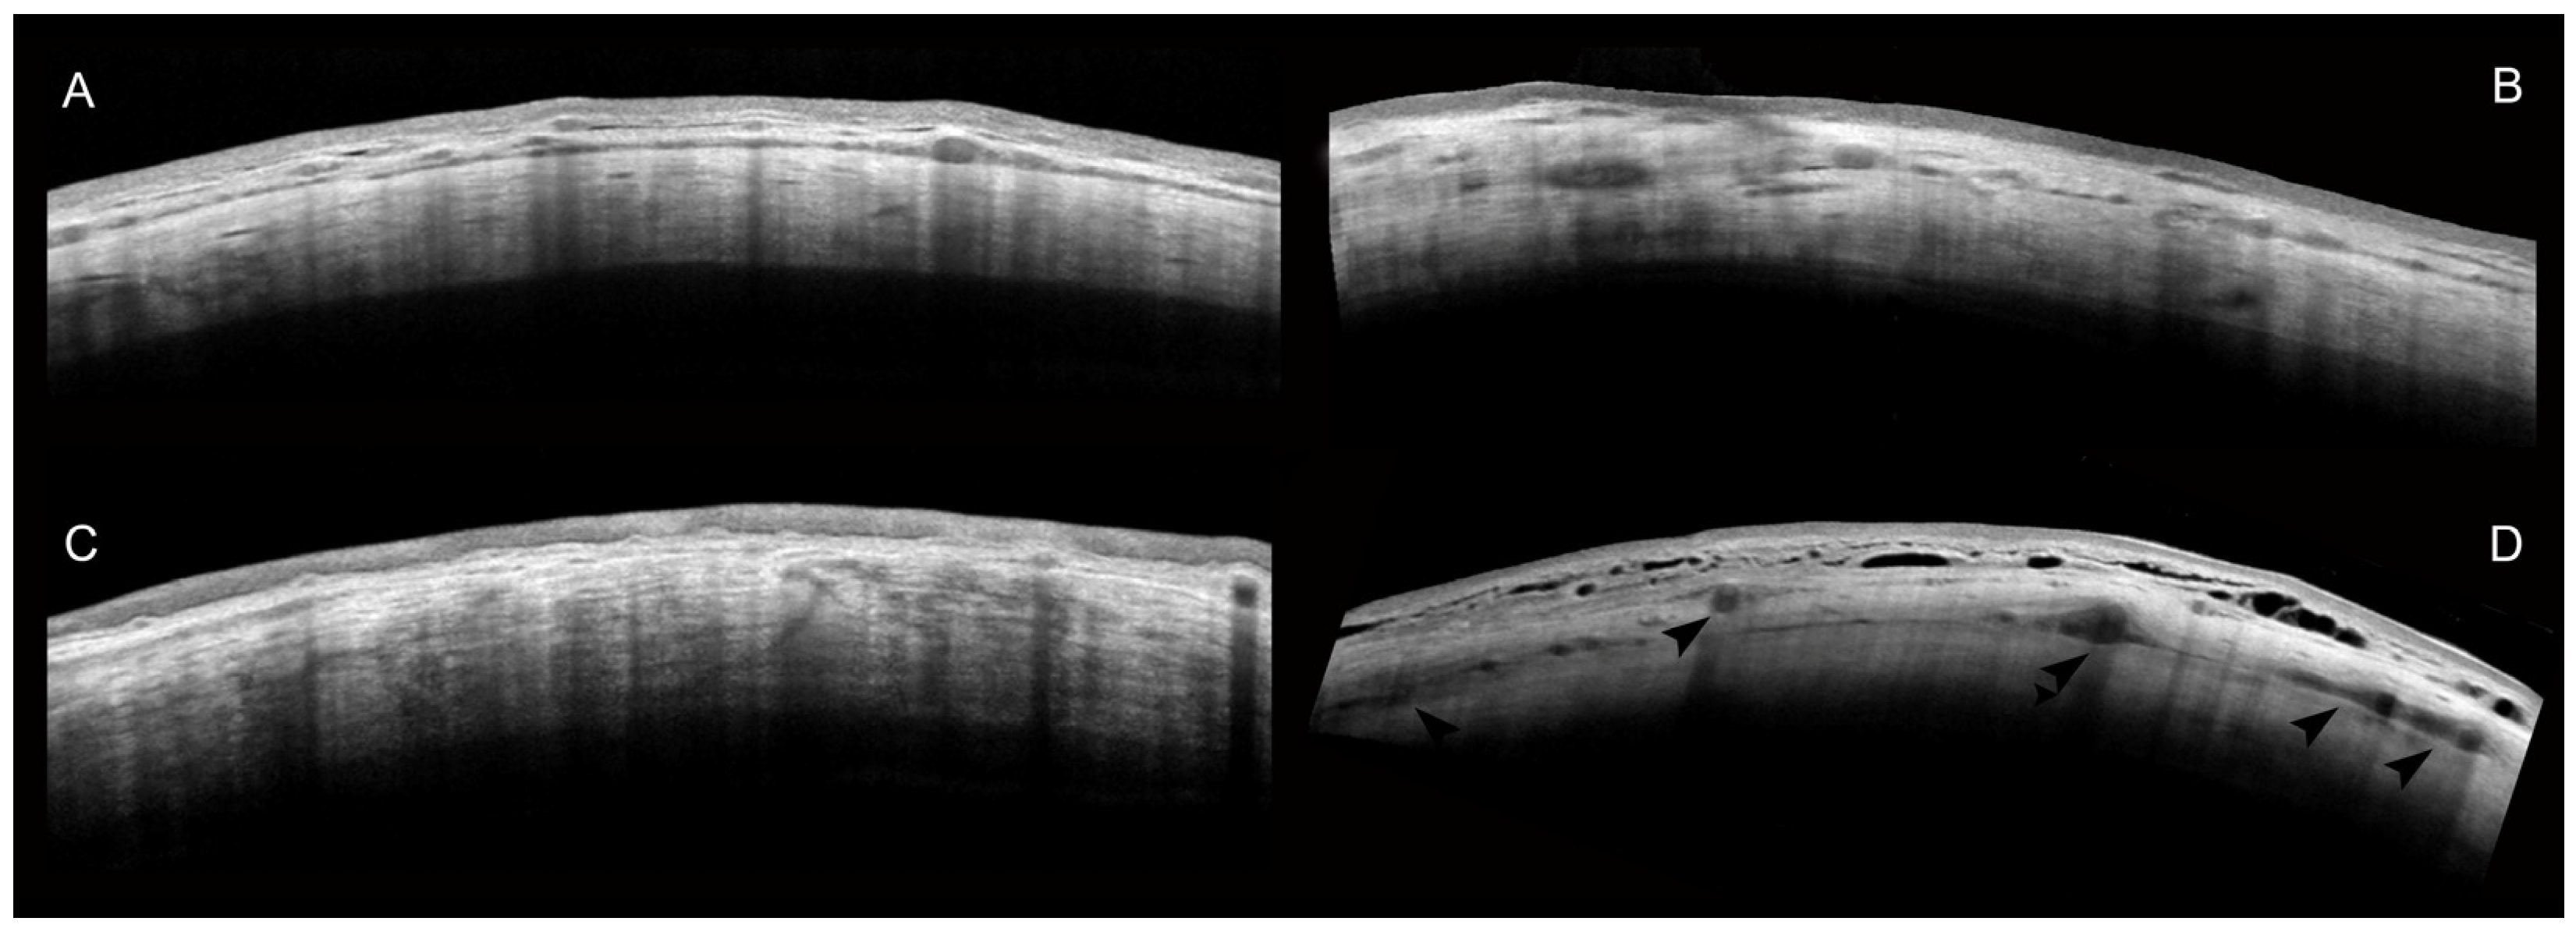

AS-OCT of the Sclera